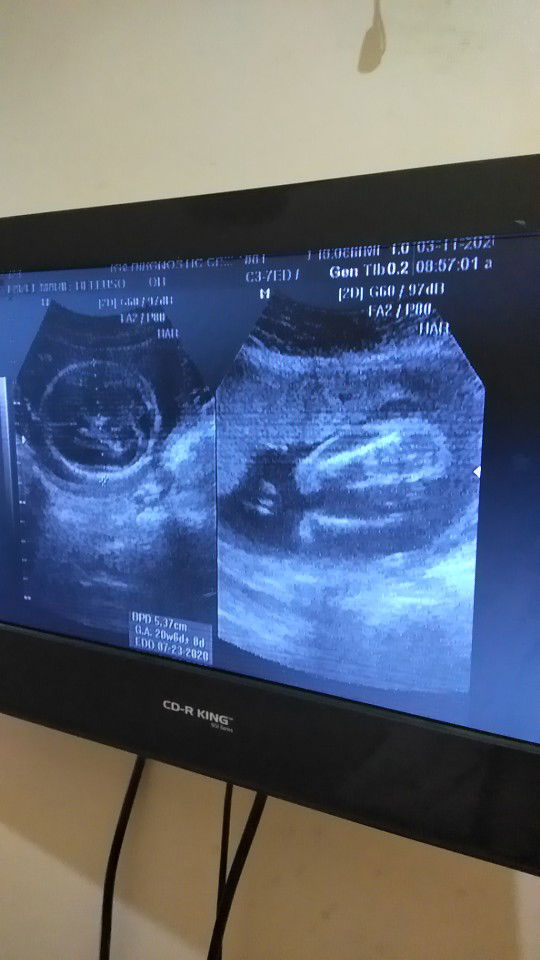

Baby girl

Sino same ng ultrasound ko mommies? ☺ baby girl daw po sabi ng sonologist 22weeks ako now. Naguluhan kasi ako dun sa neighbor ko baby girl din daw sakanya nung una tas pinabalik sya 7-8mos. lalake na nakita. Pagkalabas ng baby lalake nga ? possible pa ba magkamali sa 22weeks gender? Thank you!

Yung sa utz ko kasi nakabukaka sya eh kita bilat haha

Ako din momsh, uulit nalang ako pag 7mos. Pero yung sa video kasi nakabukaka sya talaga kitang kita yung bilat nya hahaha